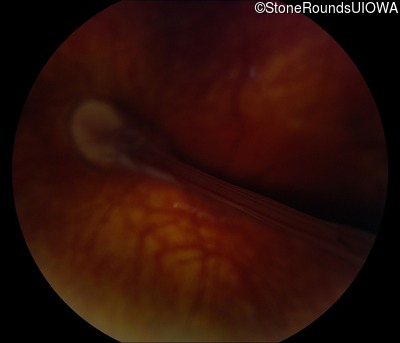

Fundus Photography - Left - 20/200

Exemplar